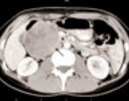

Gastric Obstruction

John C. Rhee, MD

<div id="article-content-body"><p><img src="/sites/default/files/images/Gastric%20Outlet%20Obstruction2.jpg" style="float: left; margin-left: 8px; margin-right:...